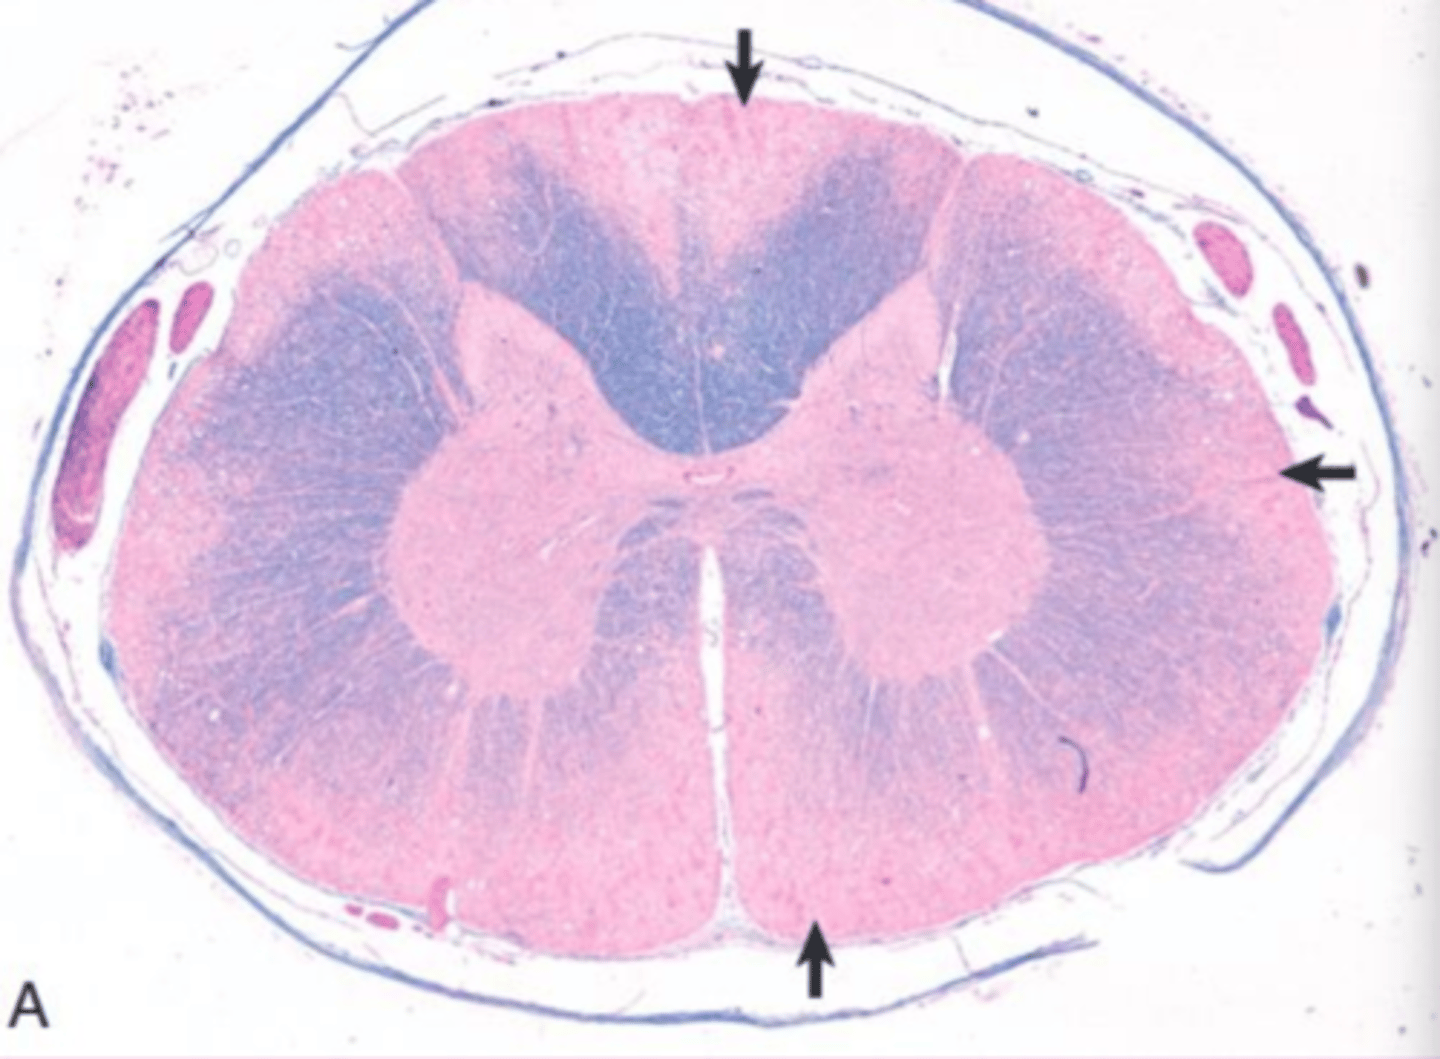

induced storage diseases

What do you call an inhibition of enzymes due to outside sources like the ingestion of locoweed

lysosomal alpha mannosidase

what is inhibited in locoweed toxicosis?

proprioceptive defects and abnormal behavior

chronic consumption of locoweed causes _________ and __________

locoweed toxicosis

if you have a goat standing around like this, and this plant is in his habitat, and his cells look like this... what do we think this is?